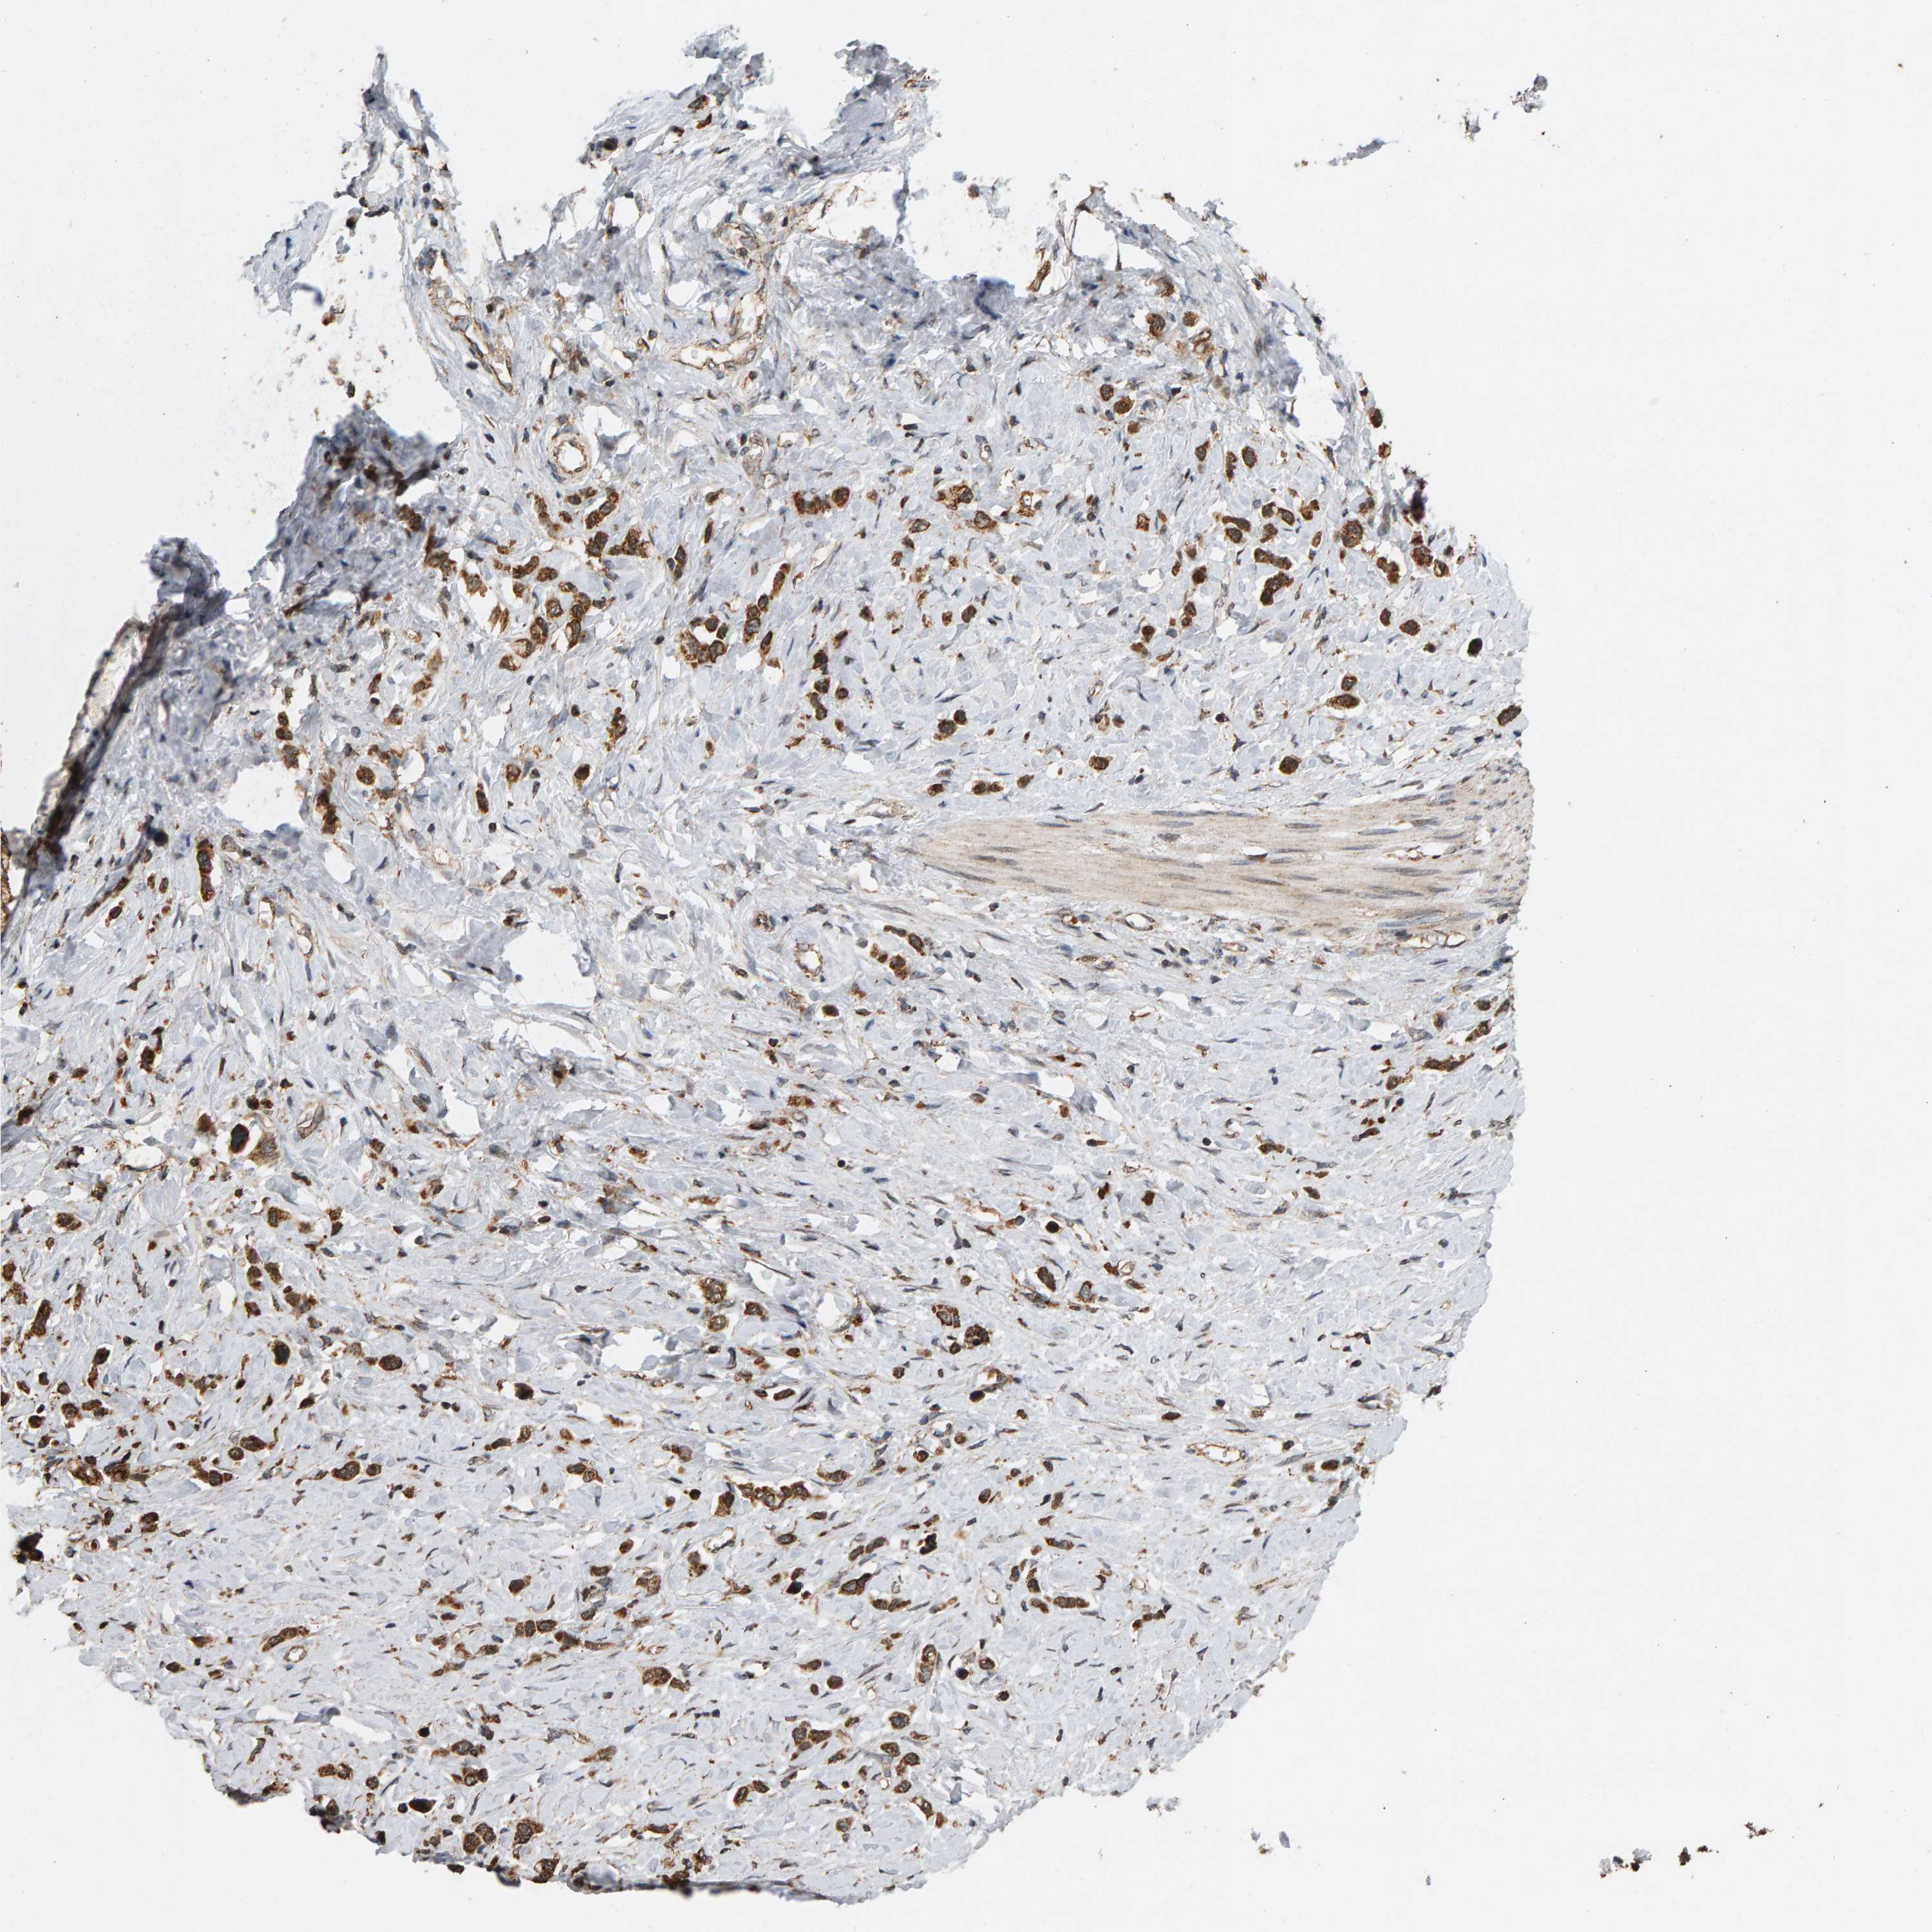

STOMACH CANCER - Protein expressioni

A mouse-over function shows sample information and annotation data. Click on an image to view it in a full screen mode. Samples can be filtered based on level of antibody staining by selecting one or several of the following categories: high, medium, low and not detected. The assay and annotation is described here.

Note that samples used for immunohistochemistry by the Human Protein Atlas do not correspond to samples in the TCGA dataset.

Antibody stainingi

Antibody staining in the annotated cell types in the current human tissue is reported as not detected, low, medium, or high, based on conventional immunohistochemistry profiling in selected tissues. This score is based on the combination of the staining intensity and fraction of stained cells.

Each image is clickable and will lead to virtual microscopy that enables deeper exploration of all samples and also displays staining intensity scores, fraction scores and subcellular localization as well as patient and tissue information for each sample.

Antibody HPA006311

Antibody HPA022904

Staining

High

Medium

Low

Not detected

Intensity

Strong

Moderate

Weak

Negative

Quantity

>75%

75%-25%

<25%

None

Location

Nuclear

Cytoplasmic/membranous

Cytoplasmic/membranous,nuclear

Adenocarcinoma, NOS

Adenocarcinoma, High grade